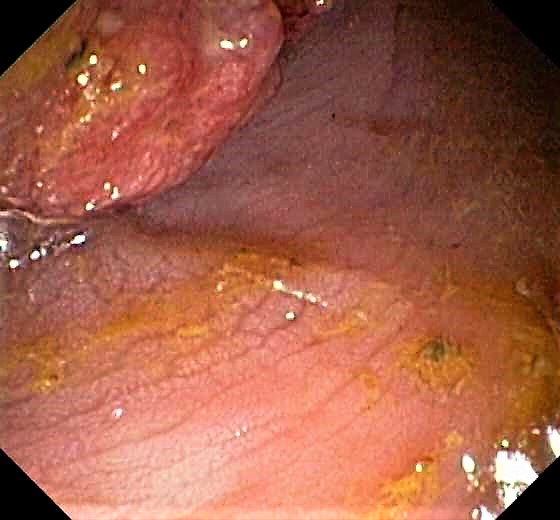

Colon Cancer (Adenocarcinoma) with Chicken Skin Mucosa

Slight Mucosal Changes are frequently seen adjacent to a colorectal cancer or adenoma. First described by Shatz BA et al, they are called Chicken Skin Mucosa (CMS), and are supposed to occur as a result of fat accumulation in macrophages in the lamina propria adjacent to colonic neoplasms. In a series of 852 consecutive colonoscopies CMS was found adjacent to eight of 10 distal colorectal cancers, one of four of proximal colon cancers and 16 of 42 distal adenomas.